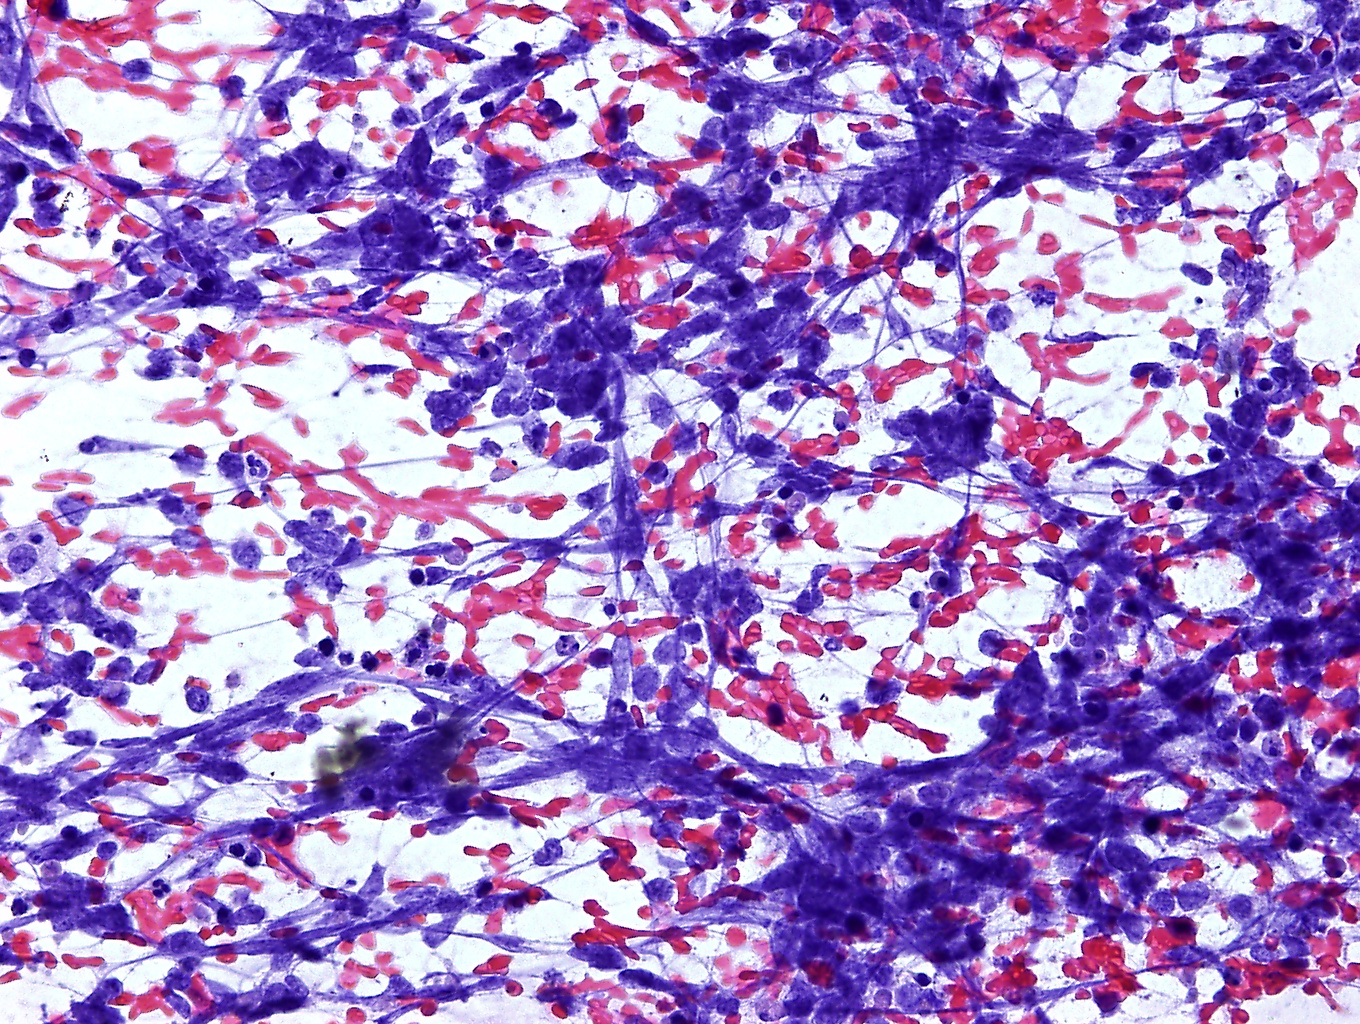

The left inguinal region was investigated, to rule out any regional lymph-node metastasis. In the groin we could find an enlarged lymph-node, measuring 34x14 mm. This lymph-node exhibit a focal hypoechoic nodule in the cortex, which measured 20x11 mm. At power-Doppler imaging this tumor deposit had an intense and anarchic vascularization. A sonography-guided fine-needle aspiration (FNA) of the focal nodule was carried out. Cytology and immunocytology evaluation allowed to diagnose a lymph-node metastasis from Merkel cell carcinoma (MCC).

figure 4. Cytology (Papanicolaou coloration) and immunocytology (CD56 marker) of the inguinal lymph-node showing MCC metastasis. figure 5. Contrast-enhanced CT scans showing left inguinal region lymph-node metastasis (a, arrow) and left thigh cutaneous nodule (b).